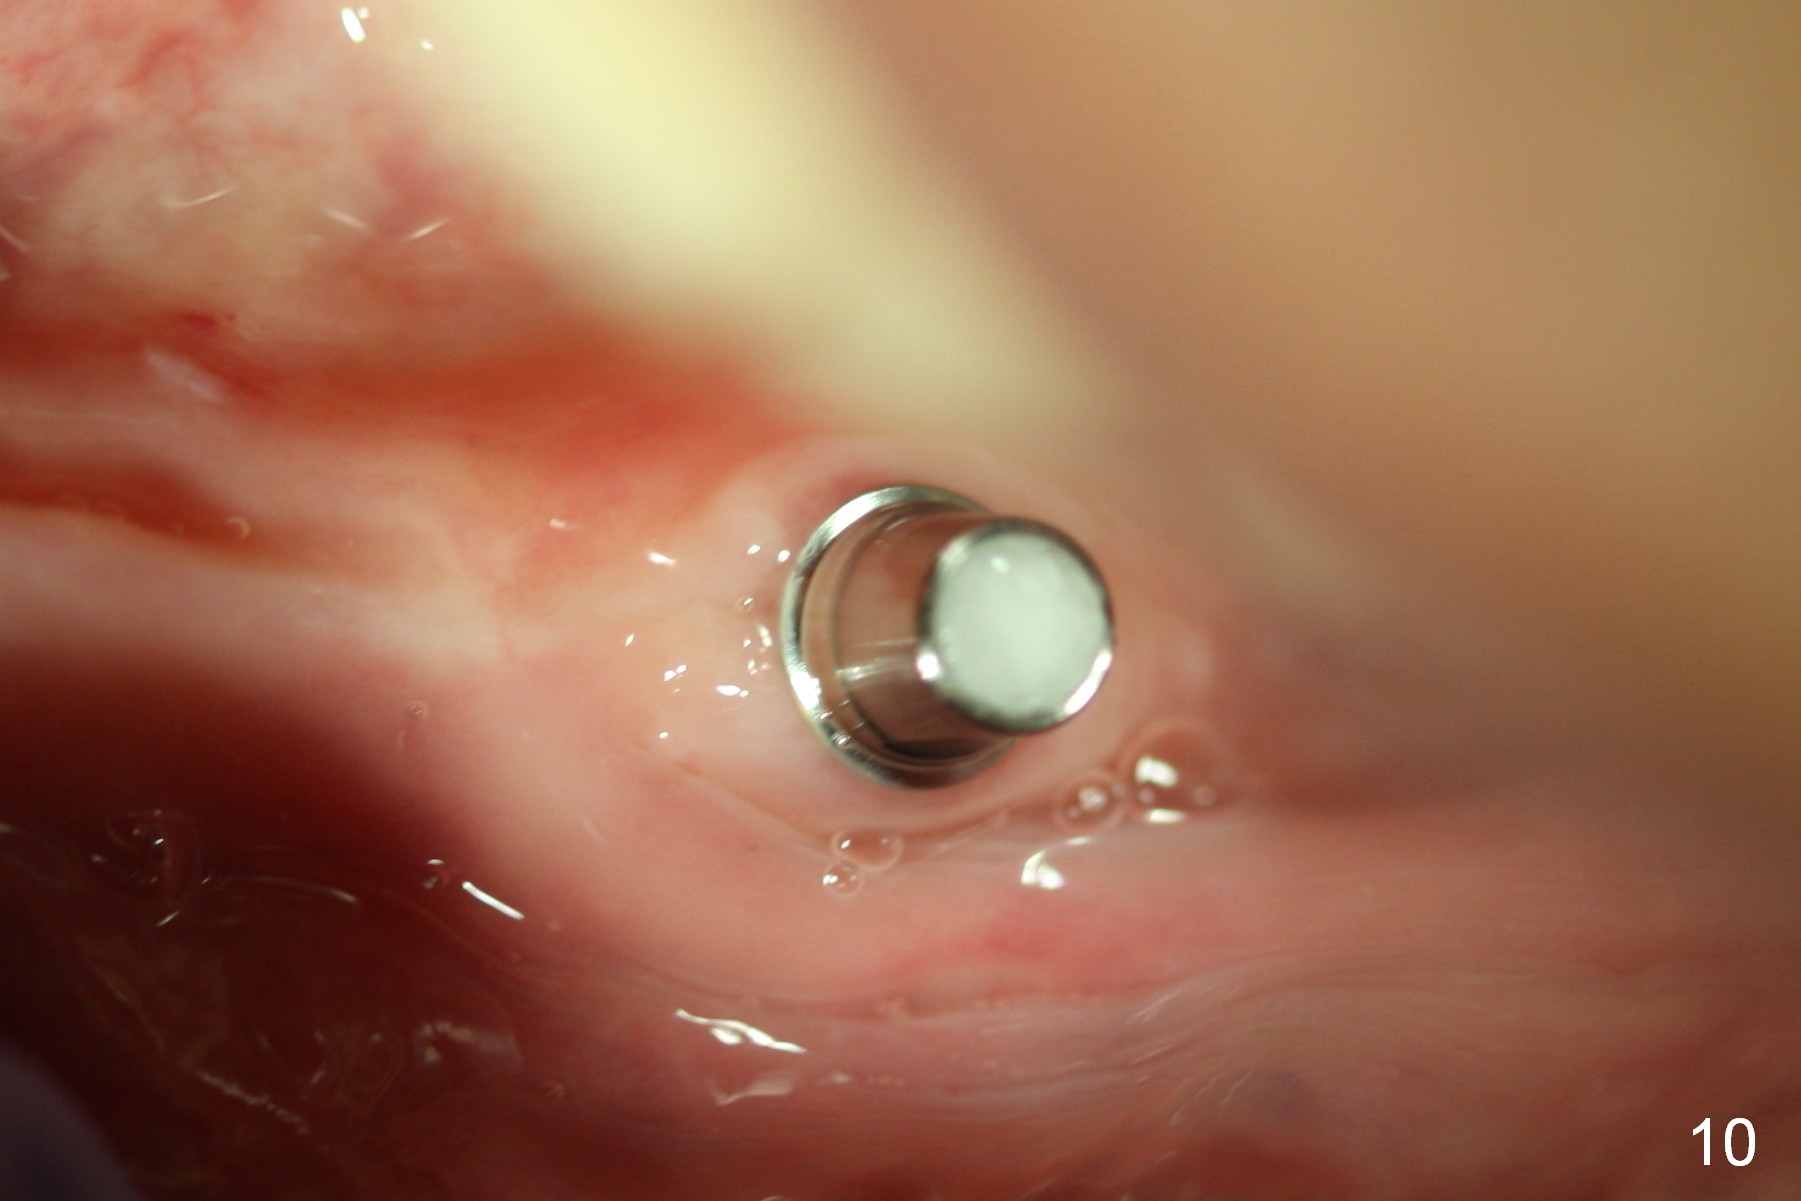

The implant osteointegrates 2 months postop (Fig.9). A pair abutment is placed (Fig.10: 5x4(2) mm) for a provisional (Fig.11). Wax up for final restorations (Fig.12-15). There is no bone resorption 1 year 4 months post cementation (Fig.16). The RPD is doing fine. The implant remains stable 3.5 years post cementation (in spite of open margin), while the other abutment for the RPD (the tooth #30) has mobility with gingival recession.